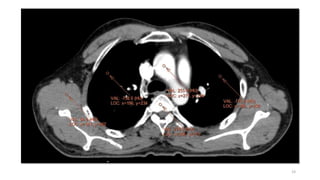

• CT

• Plain

• Contrast

• Cisternography

• CT Angio